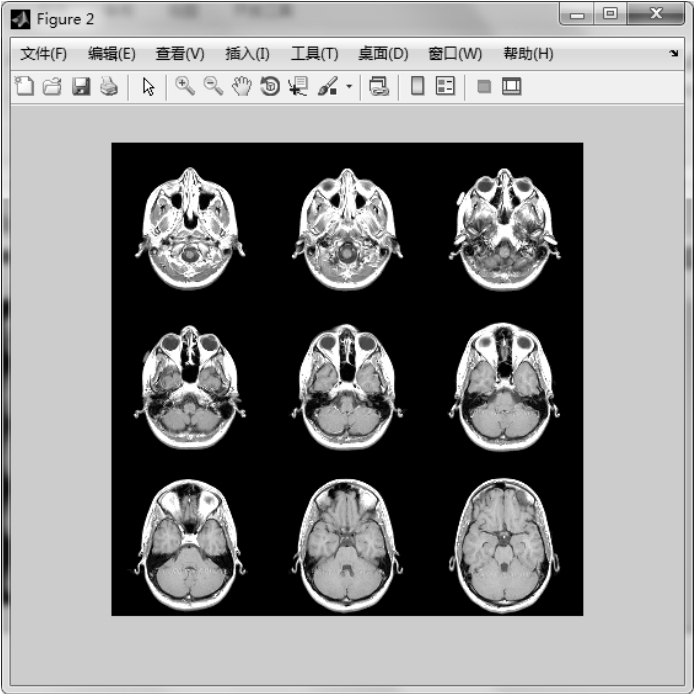

【实例3】 首先显示完整的多帧图像,然后显示前9帧图像。

图1.20 显示完整的图像序列

图1.21 显示图1.20中前9帧图像序列